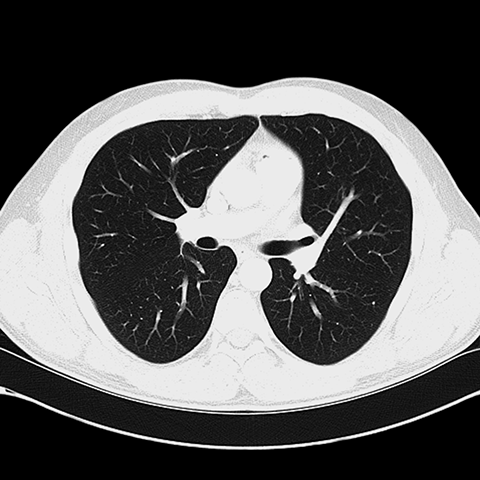

正常增强 CT(肺)Normal Contrast-Enhanced CT (Lung Window) [2 of 8]